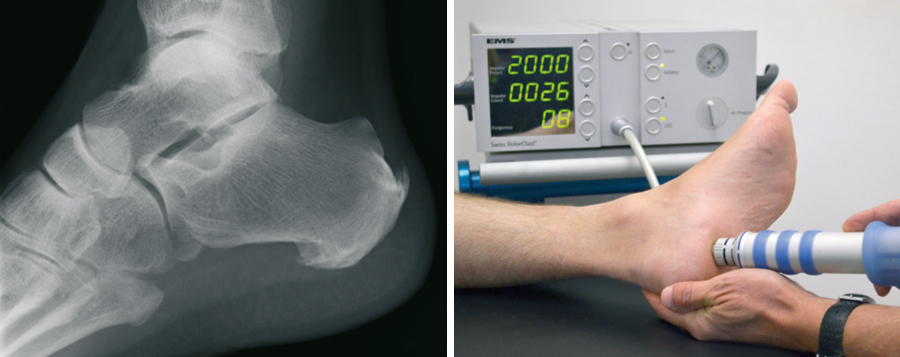

Calcaneal

The plantar Calcaneal (at the bottom of the heel) is caused by an overload of the longitudinal arch braced fascia. Connective tissue, excessive loads, malposition, but also overweight may be responsible. The congestion between the heel bone and the attachment site of this fascia is an increasing tissue damage associated with a ossification, called Calcaneal. Not the spur itself, but this tissue damage is causing the pain. They start appearing when putting pressure on it, but later also at rest. First of all the available treatments is the supply of special arch supports. Also injections directly to the Calcaneal, have their value. The shock wave therapy as proved to be very risk-free, which is carried out in our practice. Alternatively, X-ray irradiation effect healing.

Failure of all non-operating activities is also a surgical treatment option. Via a small cut at the inner edge of the heel fascia is nicked, the voltage decreases and the tissue damage can heal.

The posterior Calcaneal (back of the heel) is caused by an overload of the Achilles tendon at the base. Through the underlying calcaneus is very little space between the skin and bone. Pain or pressure damage may be the result. The beginning should be a consistent pressure relief by appropriate footwear. If this wont help the spur has to be removed surgically. For this purpose, it can sometimes be necessary to replace the approach of the Achilles tendon and fix it back to the heel bone.